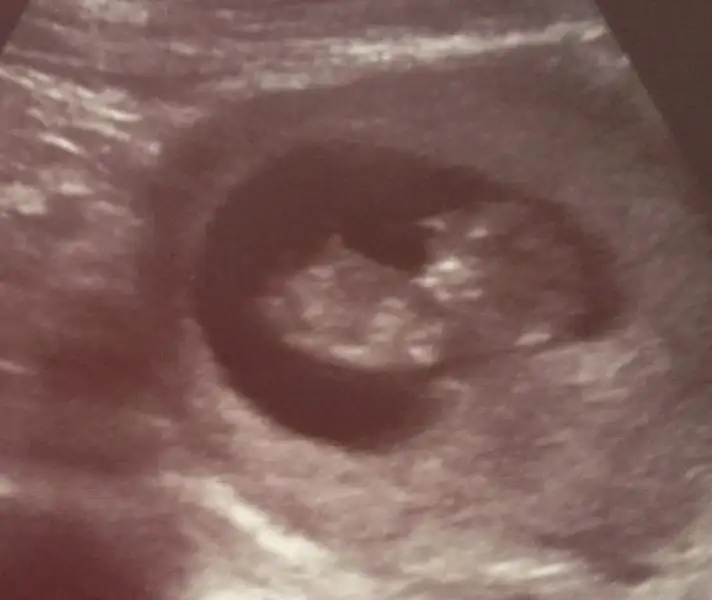

Eki Görüntüle 473837 bu benim kizim cikinti gayet net ve ortada ve ben kizim diyooo